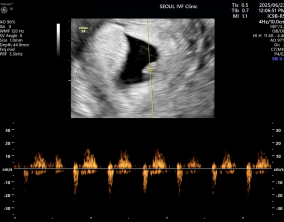

설렘과 불안의 시간을 지나 찾아온 선물

서울IVF여성의원의 난임 치료는 과정 하나하나가 체계적이고 세심하다는 인상을 받았습니다. 이유정 원장님과 간호사 분들께 치료 단계마다 충분한 설명을 들을 수 있어 불안이 많…